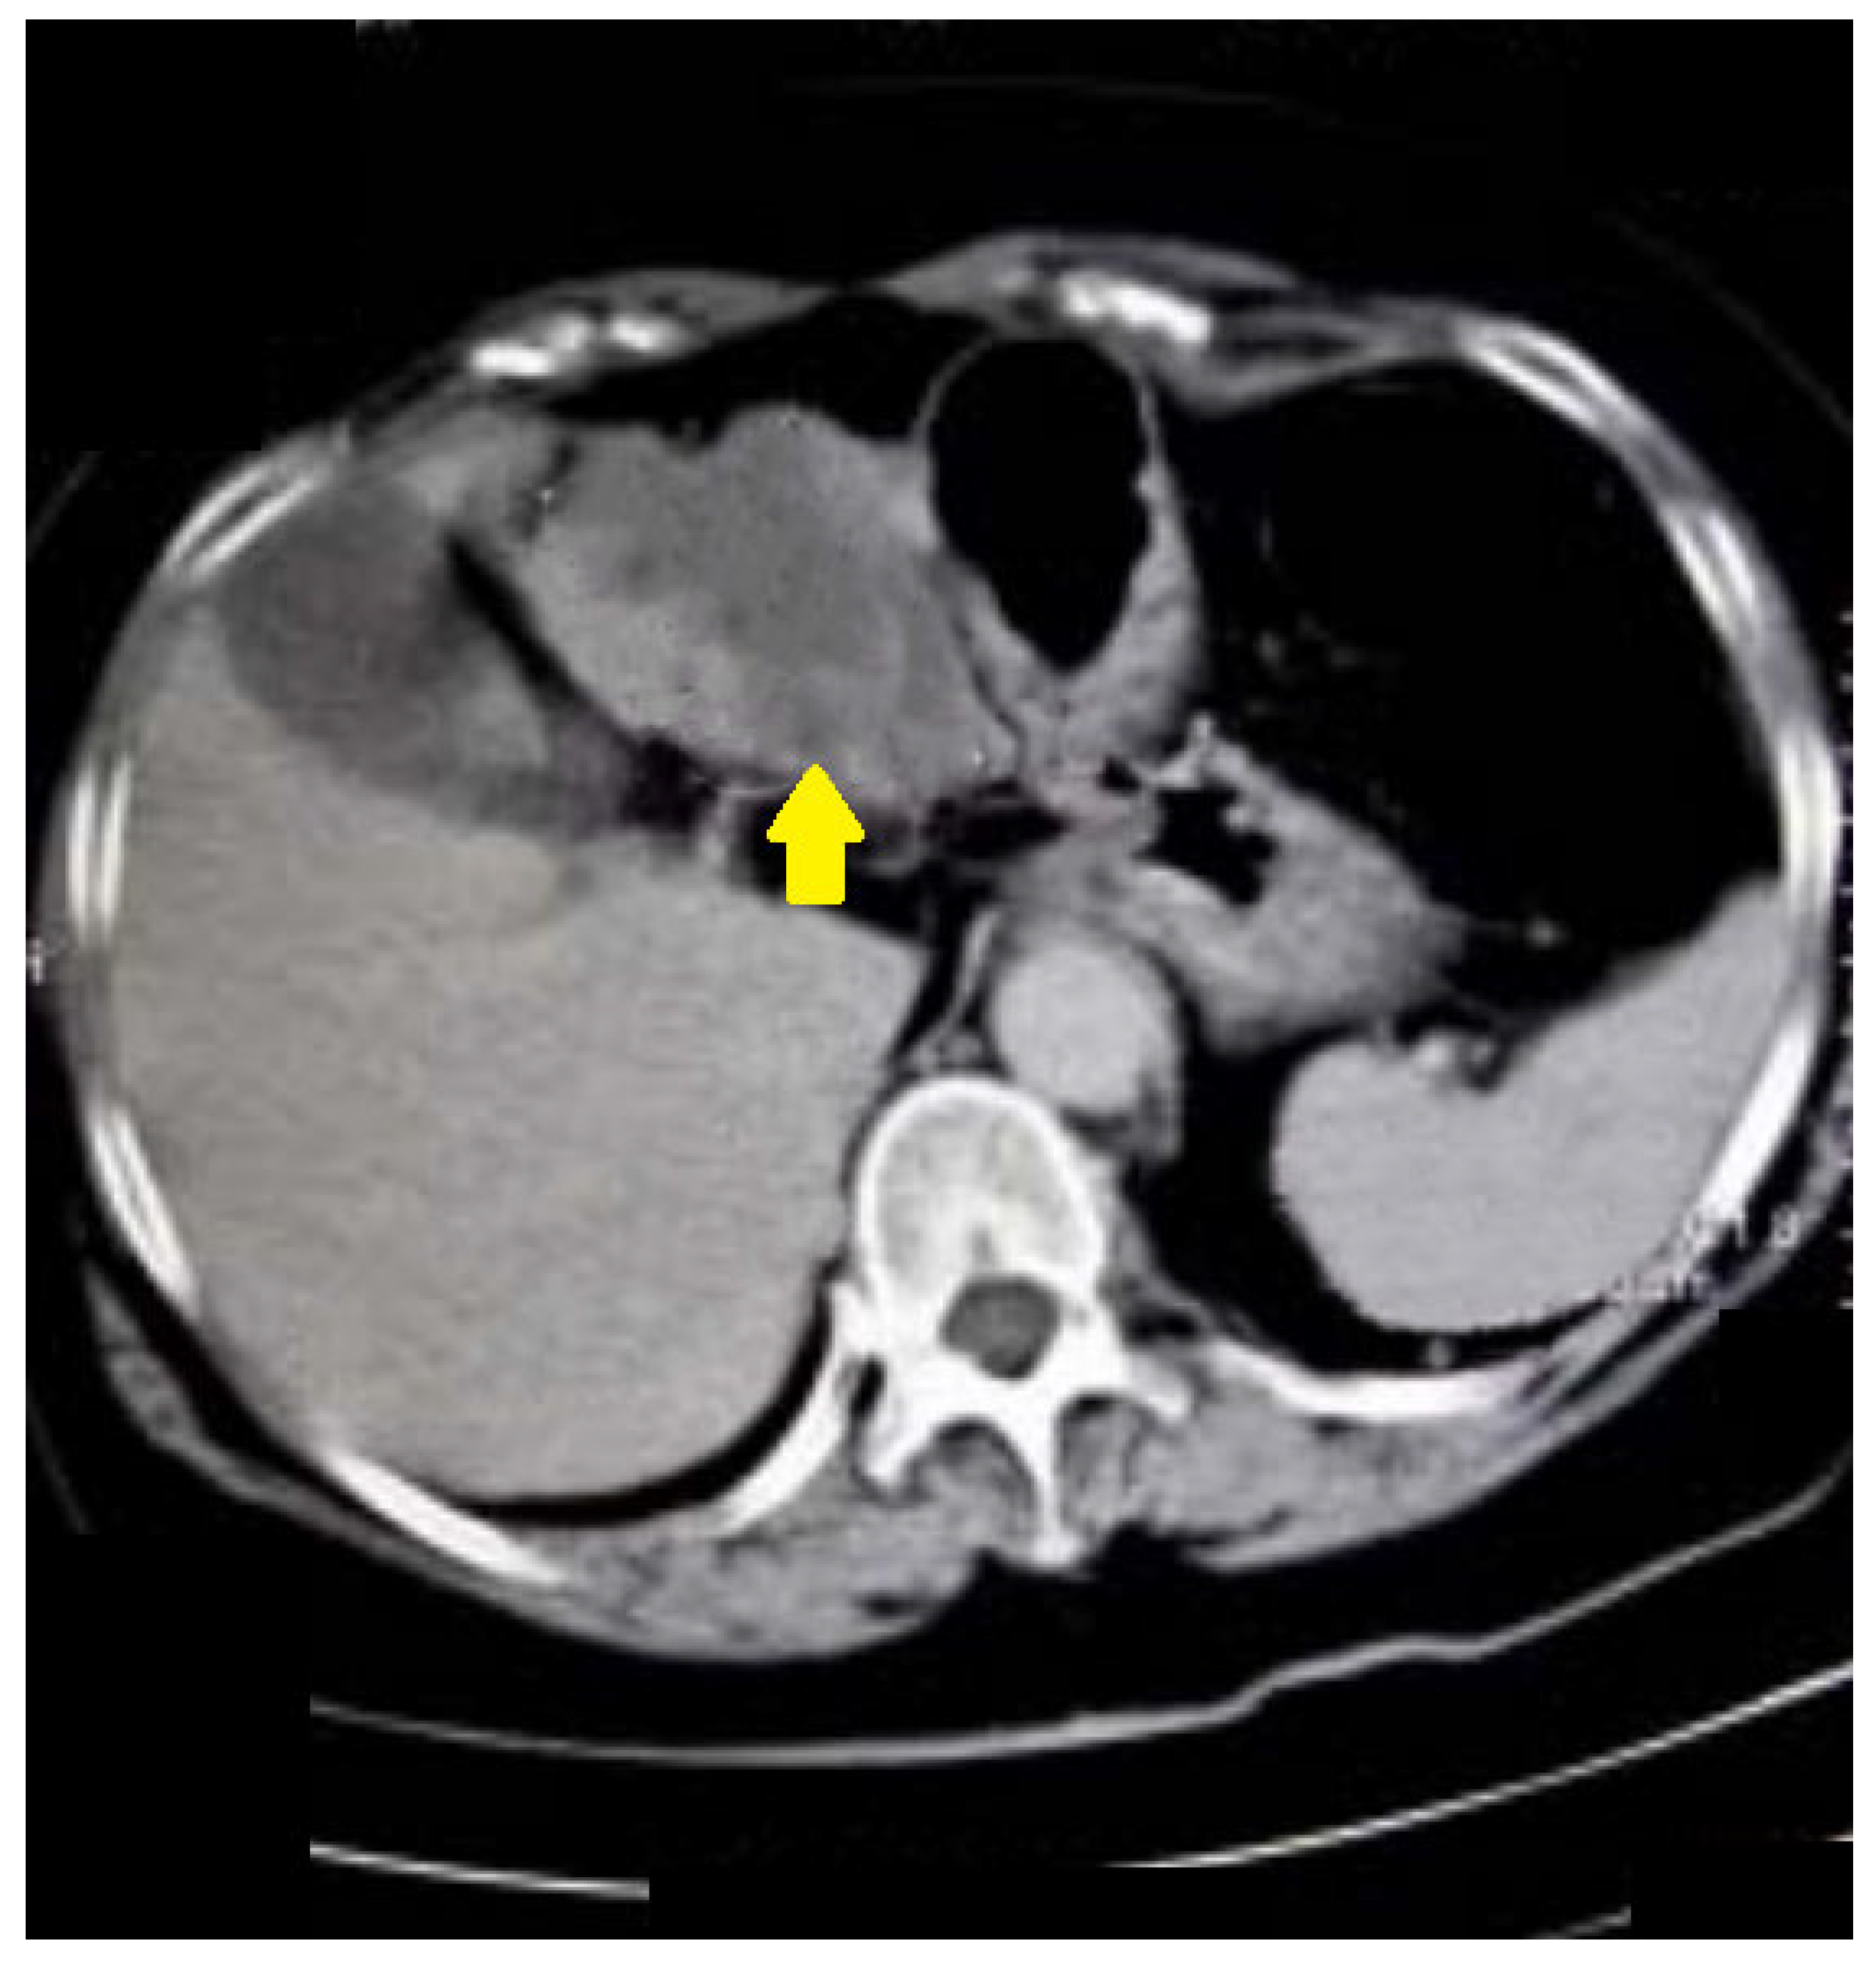

Additionally, we presented some of our patients in the group for which the virtual colonography was essential to establish the primary or other conditions. First, we presented a 73-year-old patient who had abdominal pain and constipation. The patient underwent incomplete FCS because of the stenosis of the lumen of the intestine (Figure 3). In this patient, we found tumor formation in the lumen of the colon, which arose from the intestinal wall and caused obstruction. The formation was with irregular margins and surrounded the intestine like a sleeve.

Figure 3.

CT colonography-axial scans in a supine position; 73-year-old patient with incomplete FCS due to intraluminal obturation of the sigmoid colon from carcinoma, which is presented in the figure as a tumor with soft tissue density (yellow arrow).